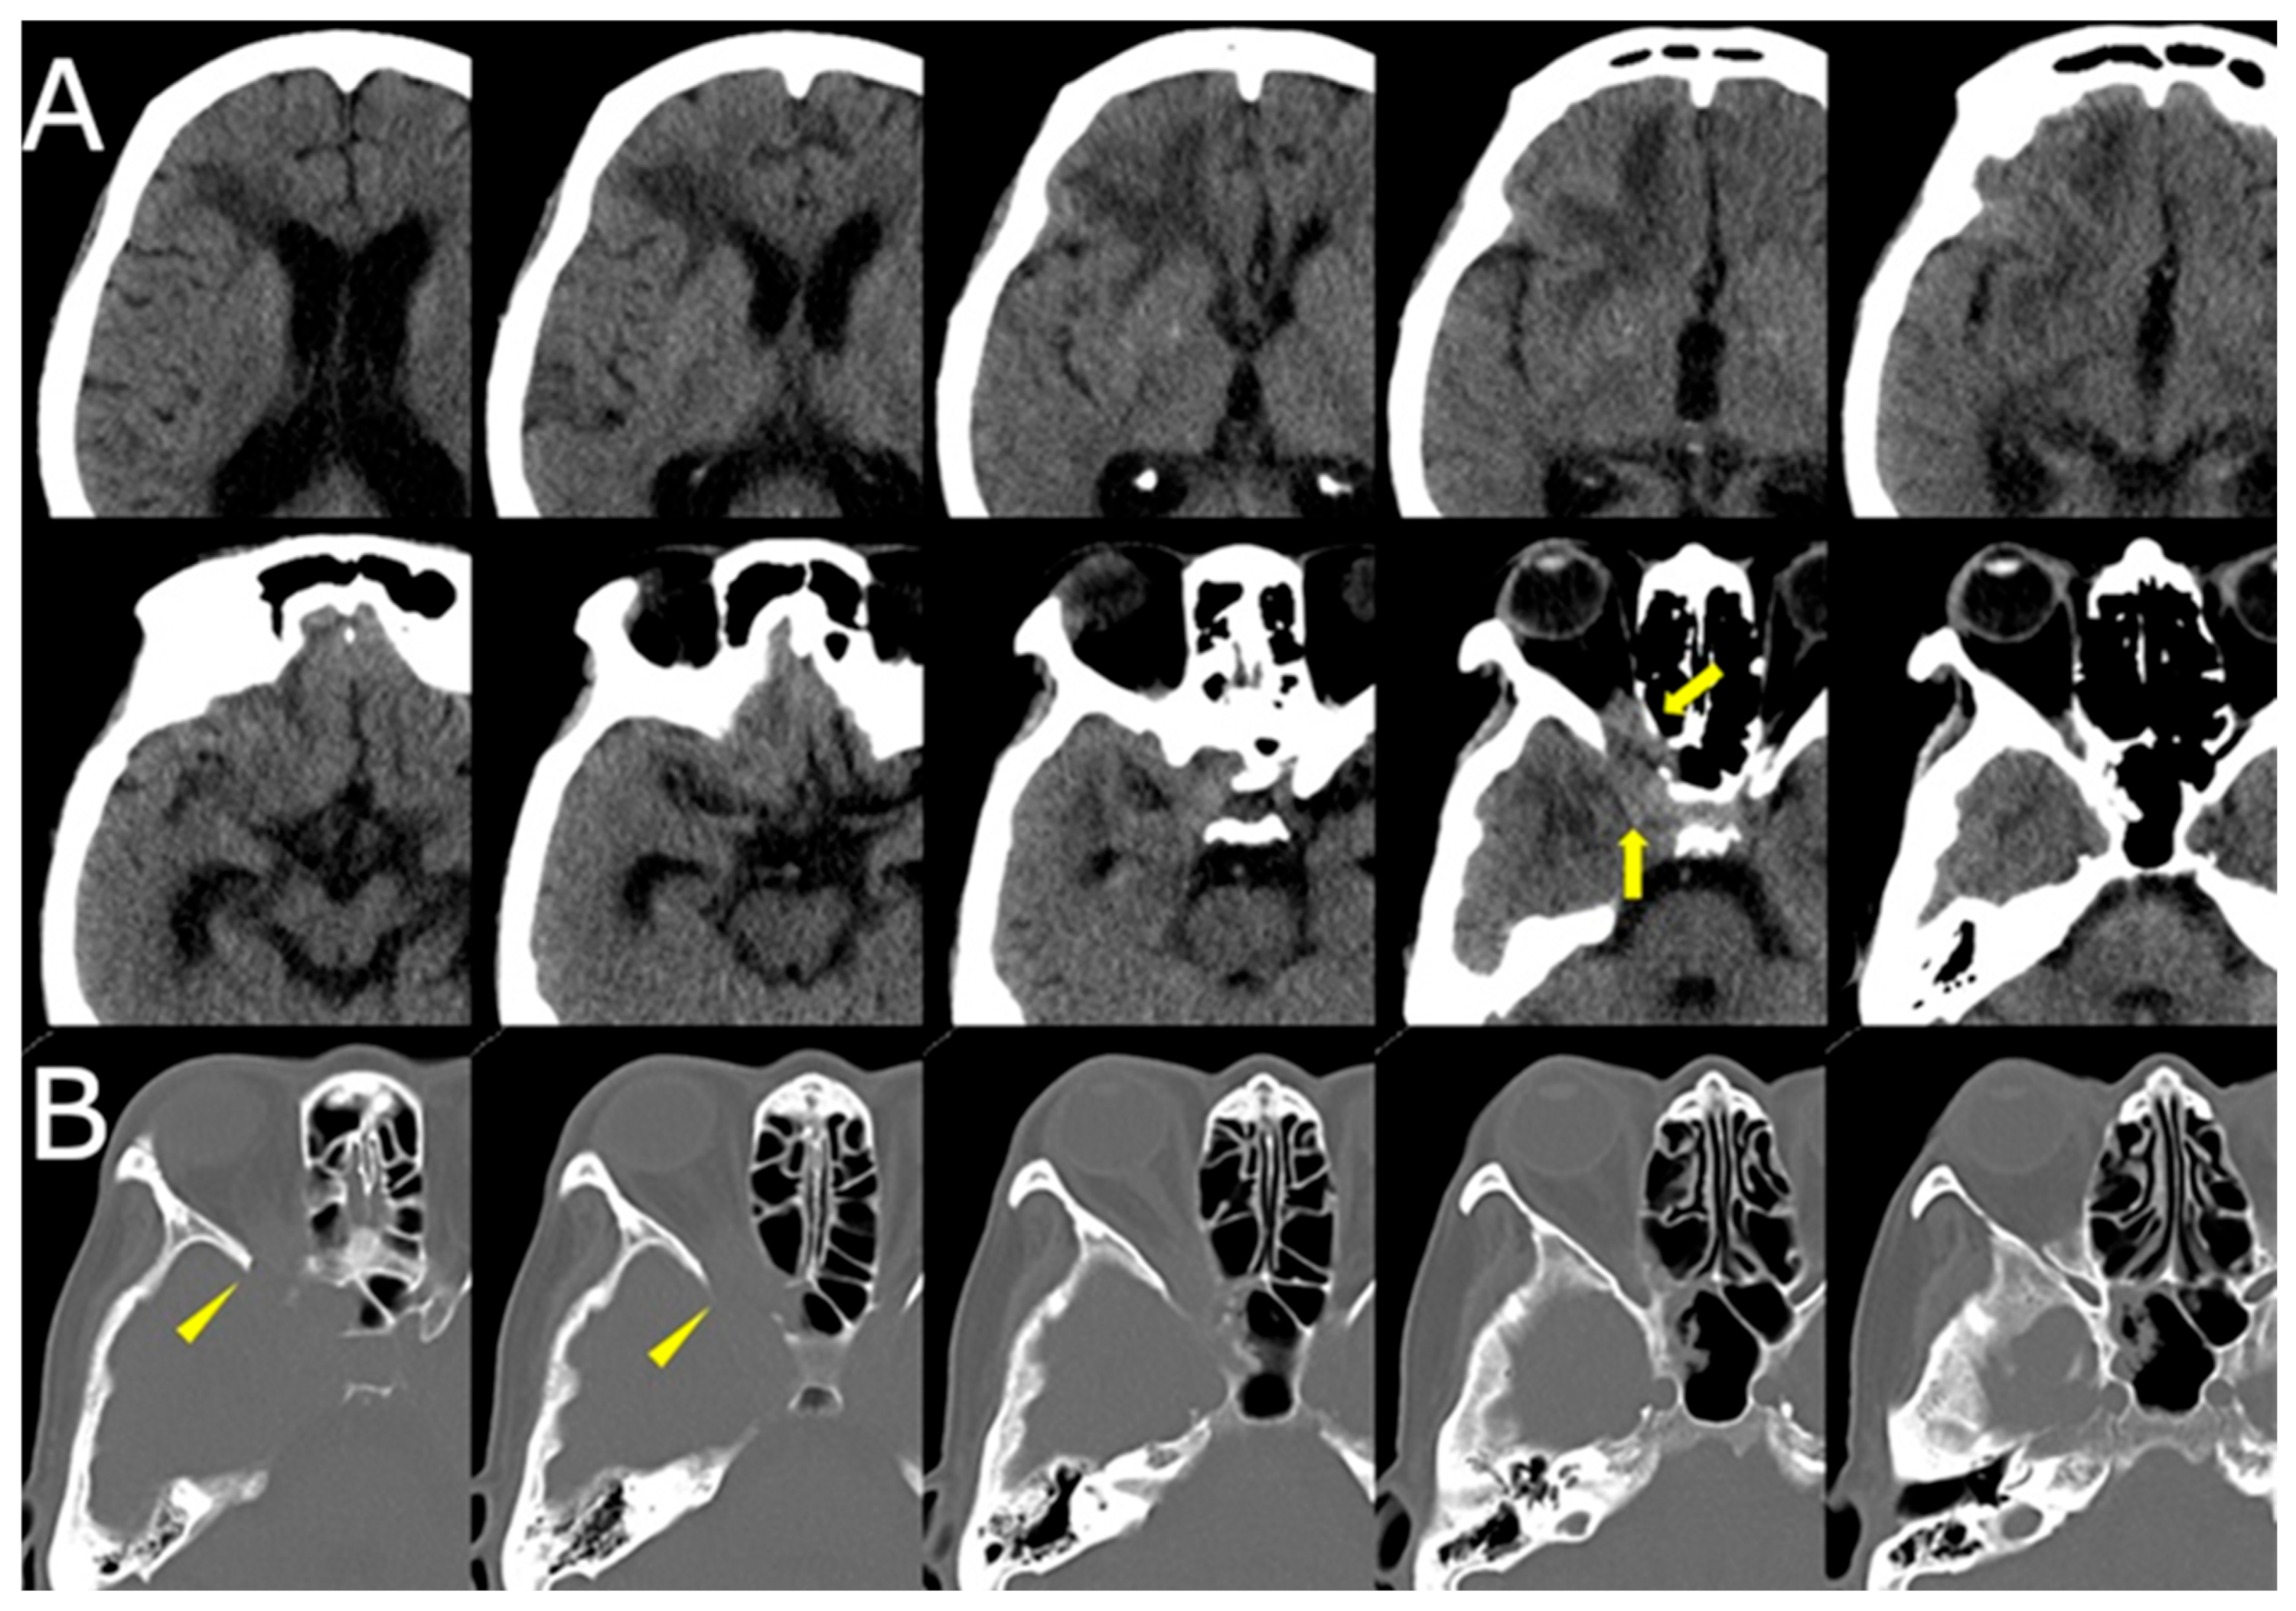

Over the following weeks, her symptoms progressed. She reported increasing difficulty in eye movement, blurred vision in the right eye, and worsening retro-orbital pain. Visual acuity in the right eye decreased to 0.3 (20/60), while the left eye remained unaffected. New findings included proptosis and chemosis without conjunctival injection. Repeat MRI revealed lesion progression into the right cavernous sinus and frontal lobe, with peripheral ring enhancement and central diffusion restriction, suggesting abscess formation. Edema in the right frontal lobe was also observed (Figure 1B, Figure 2).

CT of the sinuses demonstrated opacification of the right ethmoid and sphenoid sinuses, with bony erosion of the medial orbital wall and sinus roof (Figure 3). These findings raised suspicion for an invasive fungal process.

Figure 3. (A) Axial CT (brain window) demonstrating hypodense changes in the right frontal lobe with subtle soft tissue density in the right orbital apex and ethmoid sinus (yellow arrows). (B) CT (bone window) revealing bony erosion of the medial orbital wall and ethmoid sinus, suggesting invasive fungal involvement (yellow arrowheads).